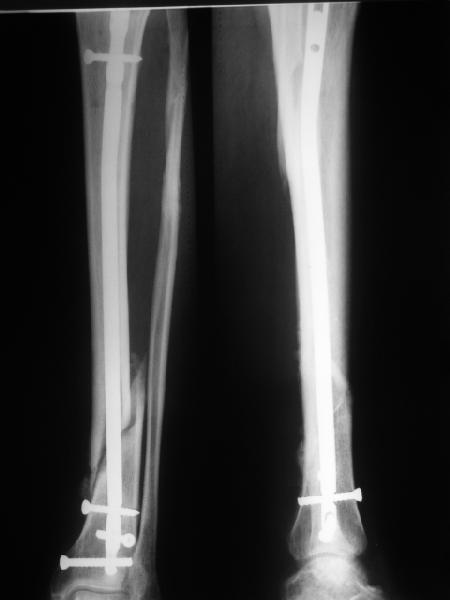

Re: неправильно фиксированный перелом

>СА> представленные снимки этому подтверждение-данный кососпиральный

СА> перелом репонируется идеально только открыто,что при БИОС не так существенно.

Здесь проблема не в идеальности репозиции, а в запасе усталостной прочности. Срастаться там может небыстро, диастазы довольно большие.

И когда еще и отломок короткий, и отверстие совсем рядом, это может привести к перелому стержня. За последние годы у нас было несколько пациентов, оперированных в других учреждениях с

подобным положением отломков, с такими переломами гвздей. И сейчас переделать куда как проще и легче, чем иметь дело со сломанным гвоздем.